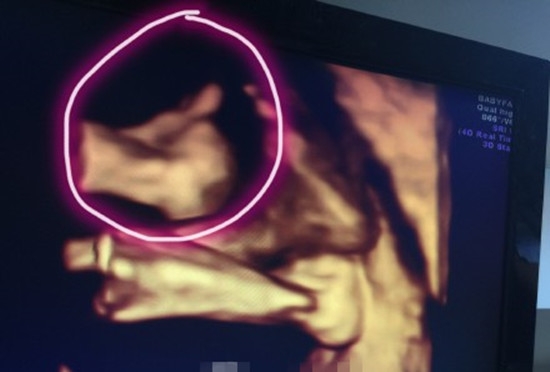

继9日林志颖公布了妻子怀双胞胎的喜讯后,10日晚,林志颖在微博晒出妻子产检时的B超照片。林志颖在微博写道:“做产检照4D,弟弟比了个赞,真是太可爱了。”看到林志颖晒出的照片,网友开始帮双胞胎起名字:“弟弟是赞米,哥哥是白米可以吗?”、“kimi真的要变成黑米哥哥了”

继9日林志颖公布了妻子怀双胞胎的喜讯后,10日晚,林志颖在微博晒出妻子产检时的B超照片。林志颖在微博写道:“做产检照4D,弟弟比了个赞,真是太可爱了。”